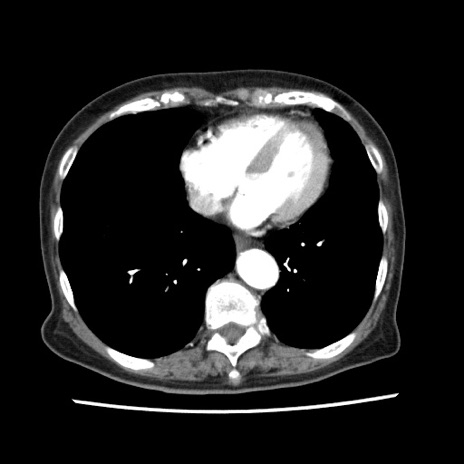

症例1(横断像)

症例

【症例】80歳代女性

【主訴】腹痛

【現病歴】8時間前から腹痛あり来院。

【既往歴】糖尿病、脂質異常症、子宮体癌にて子宮全摘術

【身体所見】意識清明・会話良好だが腹痛で苦悶様、全腹部にわたって反跳痛と圧痛あり

【データ】WBC 13600、CRP 0.14、LDH 224、CK 90